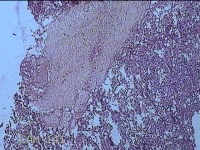

子宫腔内组织

性别

女

年龄

39岁

临床诊断

早期人工流产

一般病史

停经36天。

标本名称

大体所见

灰白暗红色不规则碎组织3x2.5x1.3cm一堆,未发现明显的绒毛样组织。

图1

不具诊断价值。

在切片质量方面还需要加把劲。